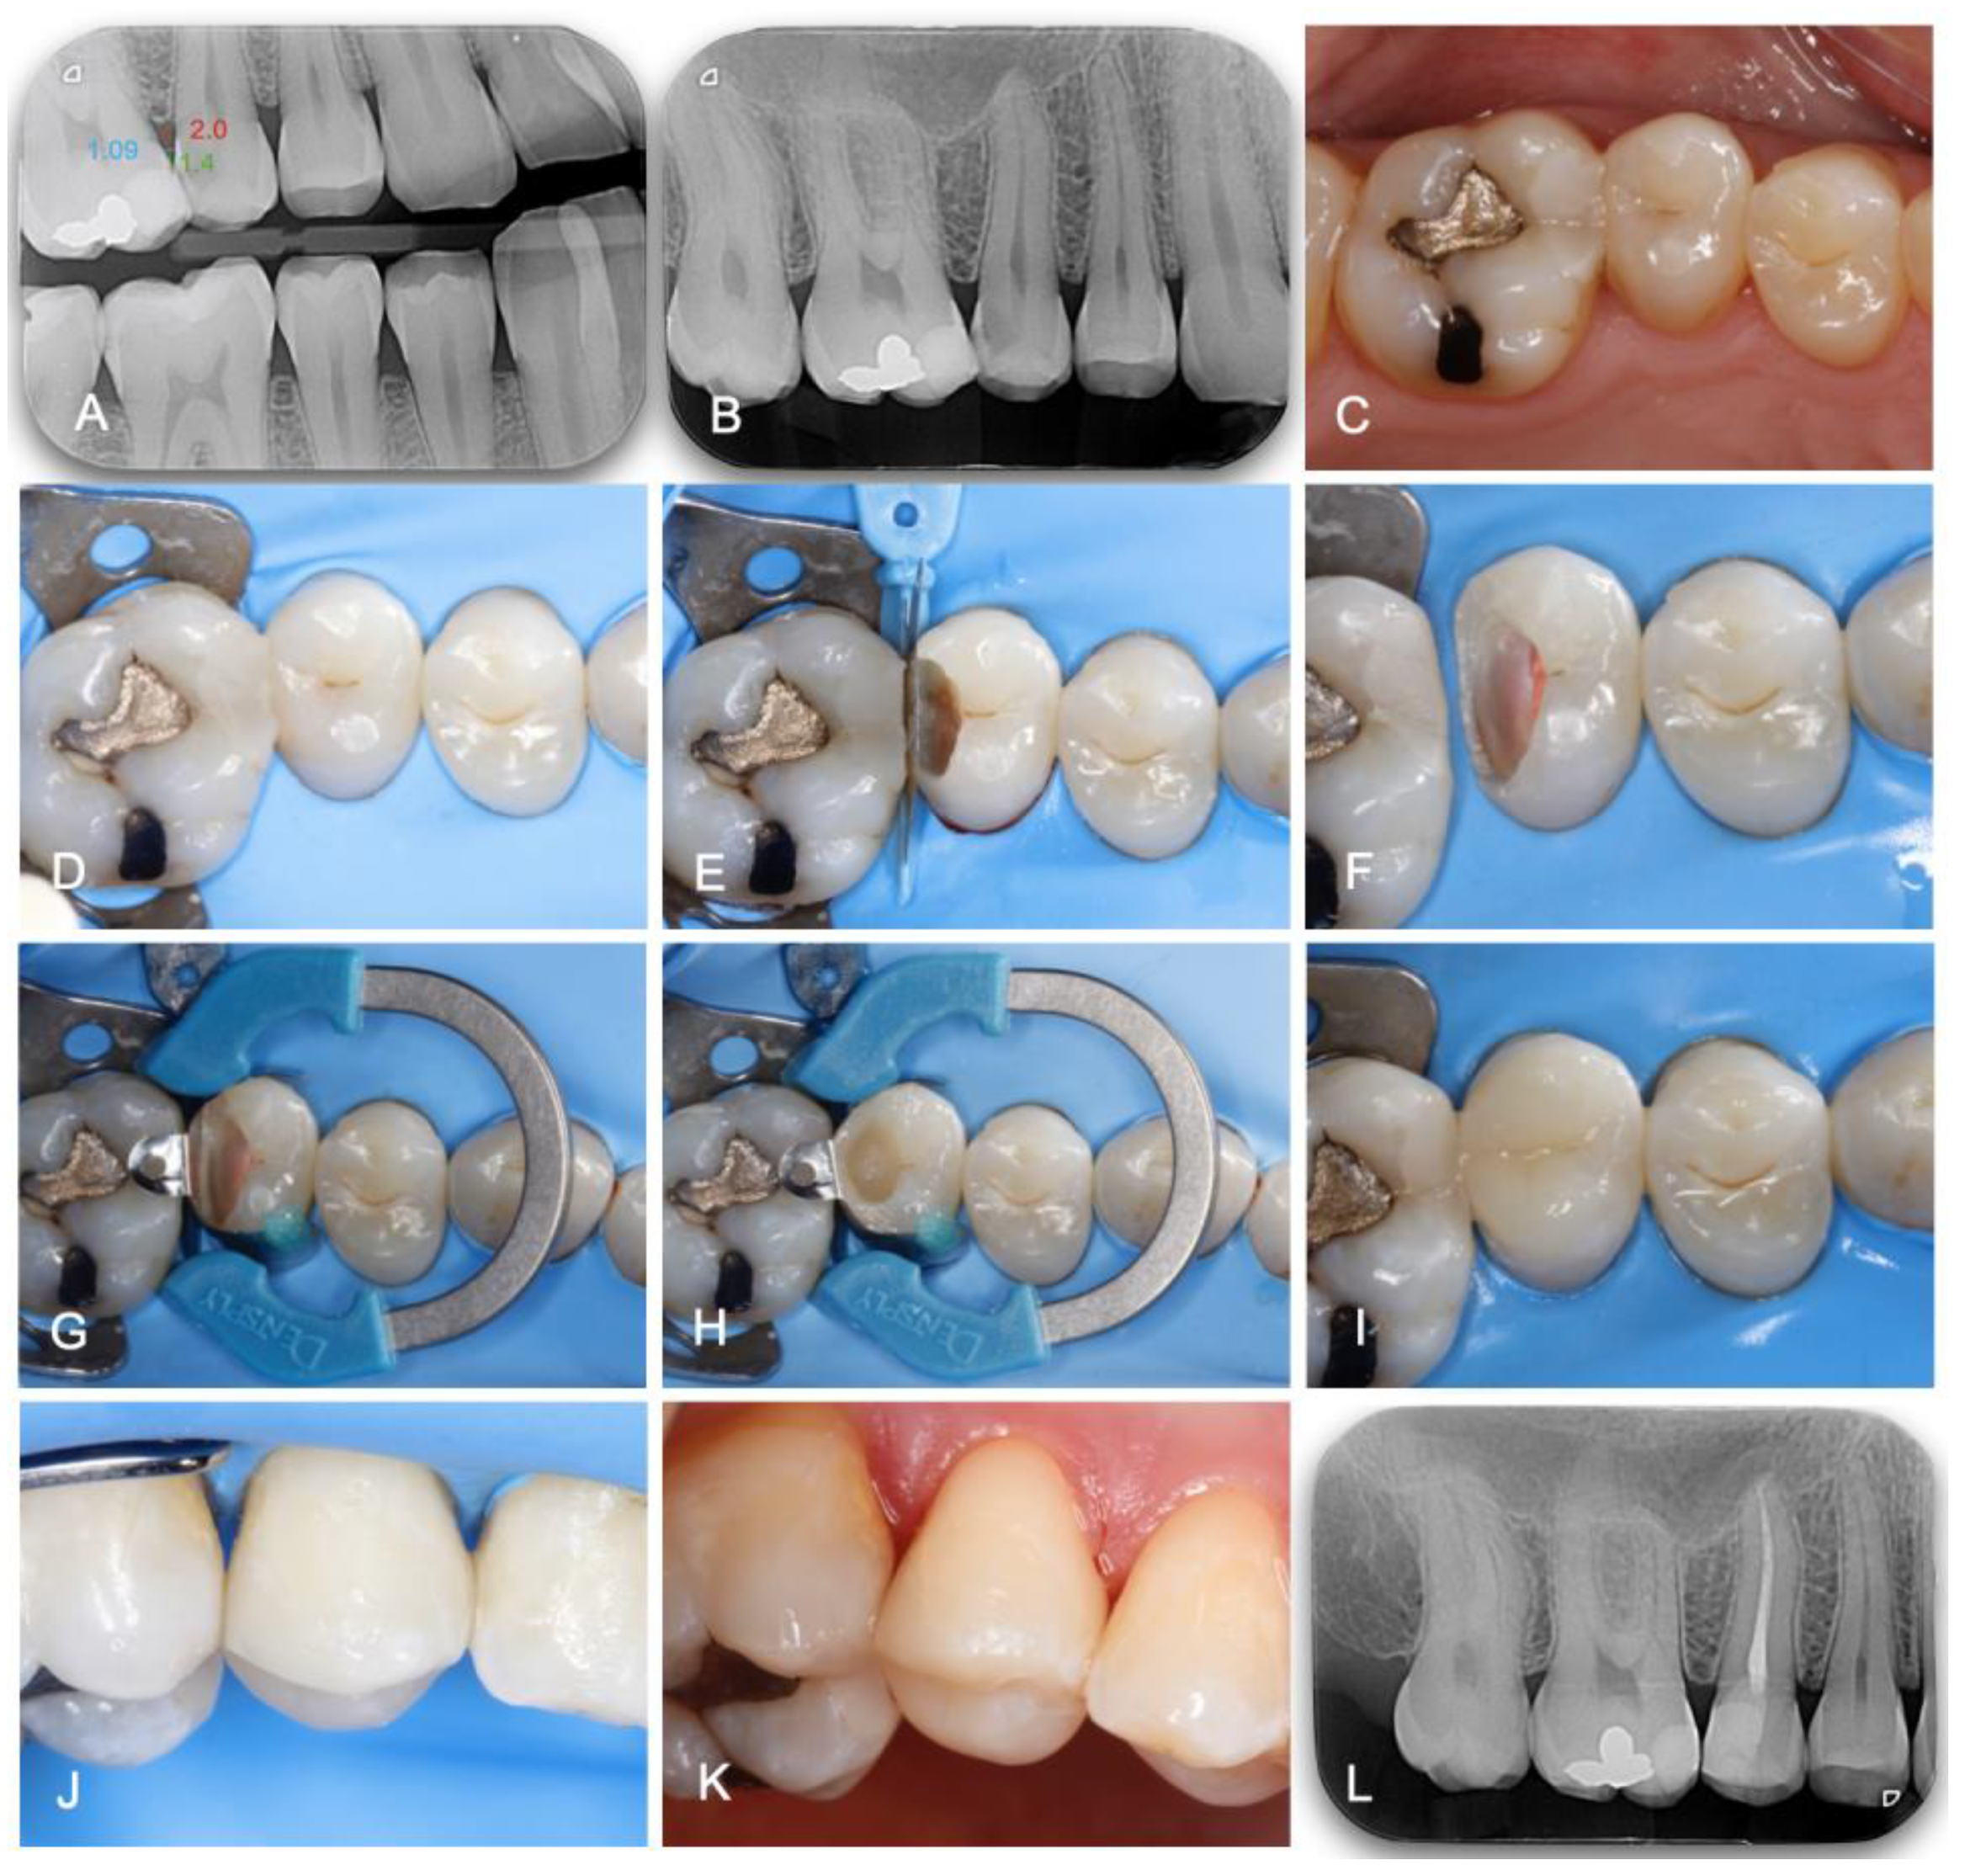

In Group 1 (n = 30), the treatment was performed using the digital method. On the preoperative bite-wing radiography, the appropriate measurements were performed as described above. According to the obtained results, the best adapted wedge was selected from the different brands used in the study. This was conducted preoperatively, after the patient’s first visit/review. The restorative procedure per se was performed in the same way as in Group 0, as shown in Figure 2. After local anesthesia, the operative field was isolated under rubber-dam (Dental Dam, Nic Tone, MDC Dental; Zapopan, Mexico). High-speed diamond burs and contra-angle tungsten carbide burs were used for caries removal. Then, a pre-contoured sectional matrix (Palodent Matrix System, Dentsply Caulk, Milford, DE, USA, thickness: 38 μm), with the previously selected wedge and a separation clamp (Dentsply Sirona, Konstanz, Germany) were placed. In case of poor fitting, as in Group 0, the wedge was replaced. A universal adhesive (3M™ Scotchbond™ Universal Plus, 3M ESPE, Seefeld, Germany) was applied under selective enamel etching. The nano-hybrid composite (Grandio; Voco, Cuxhaven, Germany) was applied in a multilayering technique. After the occlusal analysis and final polishing, the quality of the treatment was checked by clinical and radiographic inspection.

Figure 2. Clinical case where both endodontic and restorative procedures were performed in one appointment. (A) Bite-wing radiography and embrasure measurement. (B) Preoperative periapical radiography. (C) Preoperative view. (D) Isolation. (E) Pre-wedging and adjacent tooth protection. (F) Root canal treatment. (G) Placement and stabilization of the matrix. (H) Class II transformation into Class I. (IK) Final view. (L) Final bite-wing radiography.